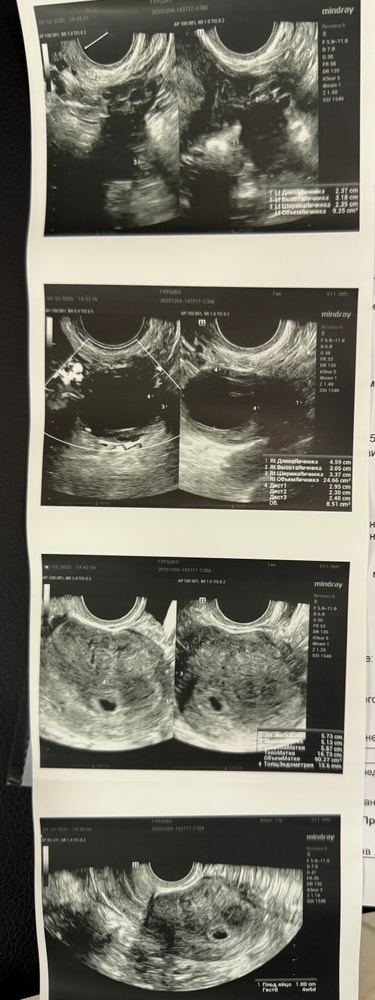

Девочки, у кого так было? Овуляция была 4-5 дней назад, поймала тестами и потом на узи желтое тело в яичнике. Сегодня сделала УЗИ, болит в боку, а в другом яичнике фолликул 24 мм. Или киста будет, или просто такой большой. Почему так? Не хватает прогестерона? У кого так было, расскажите, пожалуйста 🙏🏻

17 дц, сейчас была на узи и увидели кисту желтого тела.